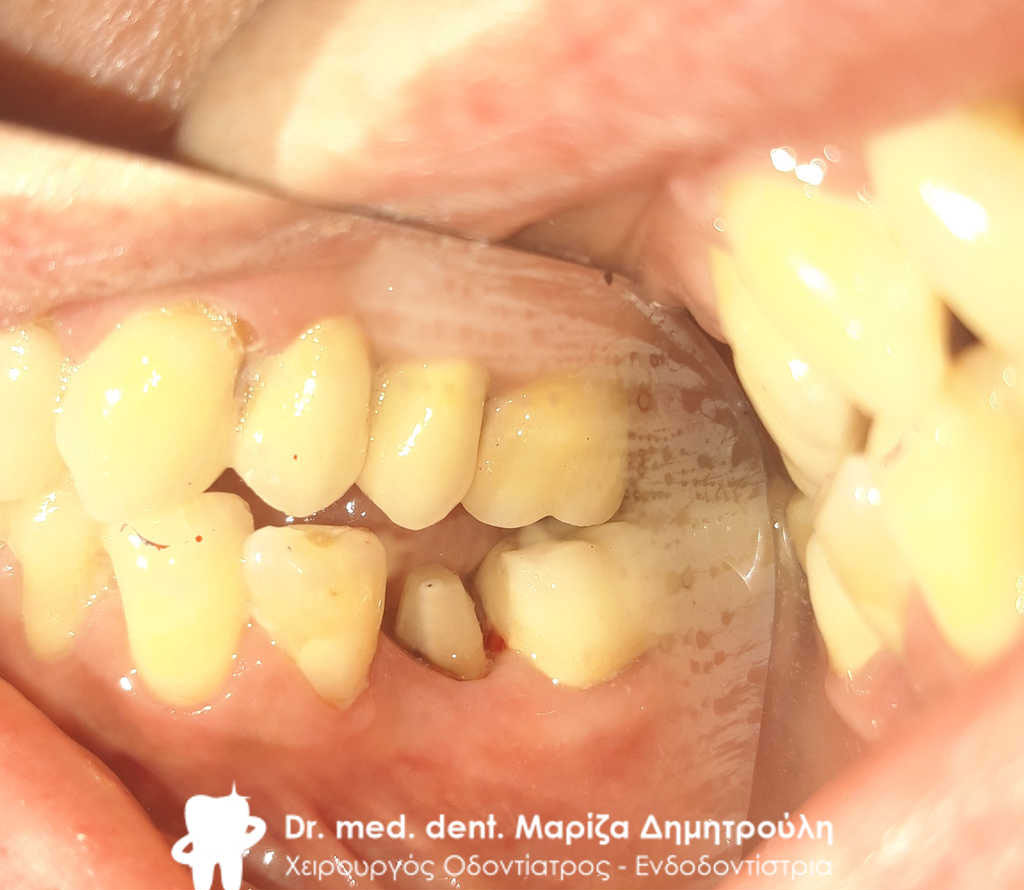

Περιστατικό – Ολοκεραμική θήκη ζιρκονίου στον αριστερο γομφίο της κάτω γνάθου

Ο πρώτος γόμφιος στην αριστερή πλευρά της κάτω γνάθου είχε απονευρωθεί στο παρελθόν. Ο ασθενής δεν θέλησε να καλύψει το δόντι με θήκη, ώστε να είναι πλήρως προστατευμένο με αποτέλεσμα το δόντι να σπάσει (όπως φαίνεται στην αρχική εικόνα). Η λύση θεραπείας ήταν η κατασκευή στεφάνης δοντιού, αφού προηγουμένως το δόντι τροχίστηκε καταλλήλως και ο οδοντοτεχνίτης κατασκεύασε την ολοκεραμική θήκη ζιρκονίου.

Το δόντι είναι πλέον πλήρως προστατευμένο και μπορεί να αντέξει στο πέρασμα των χρόνων.

ΠΡΙΝ

ΜΕΤΑ